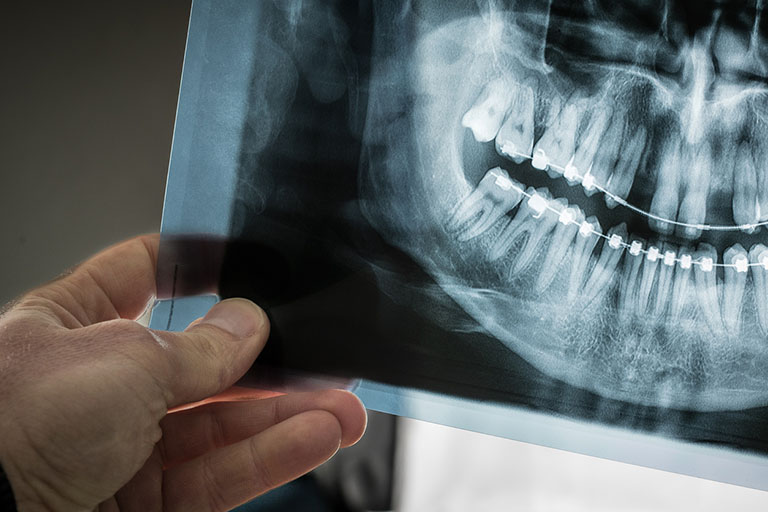

Phim toàn cảnh (Panorama)

Máy chụp sẽ quay một vòng quanh đầu bạn. Phim này cho cái nhìn tổng quát về toàn bộ hàm trên, hàm dưới, khớp thái dương hàm và xoang mũi trên cùng một tấm ảnh 2D. Thường dùng cho niềng răng, nhổ răng khôn, kiểm tra tổng quát.